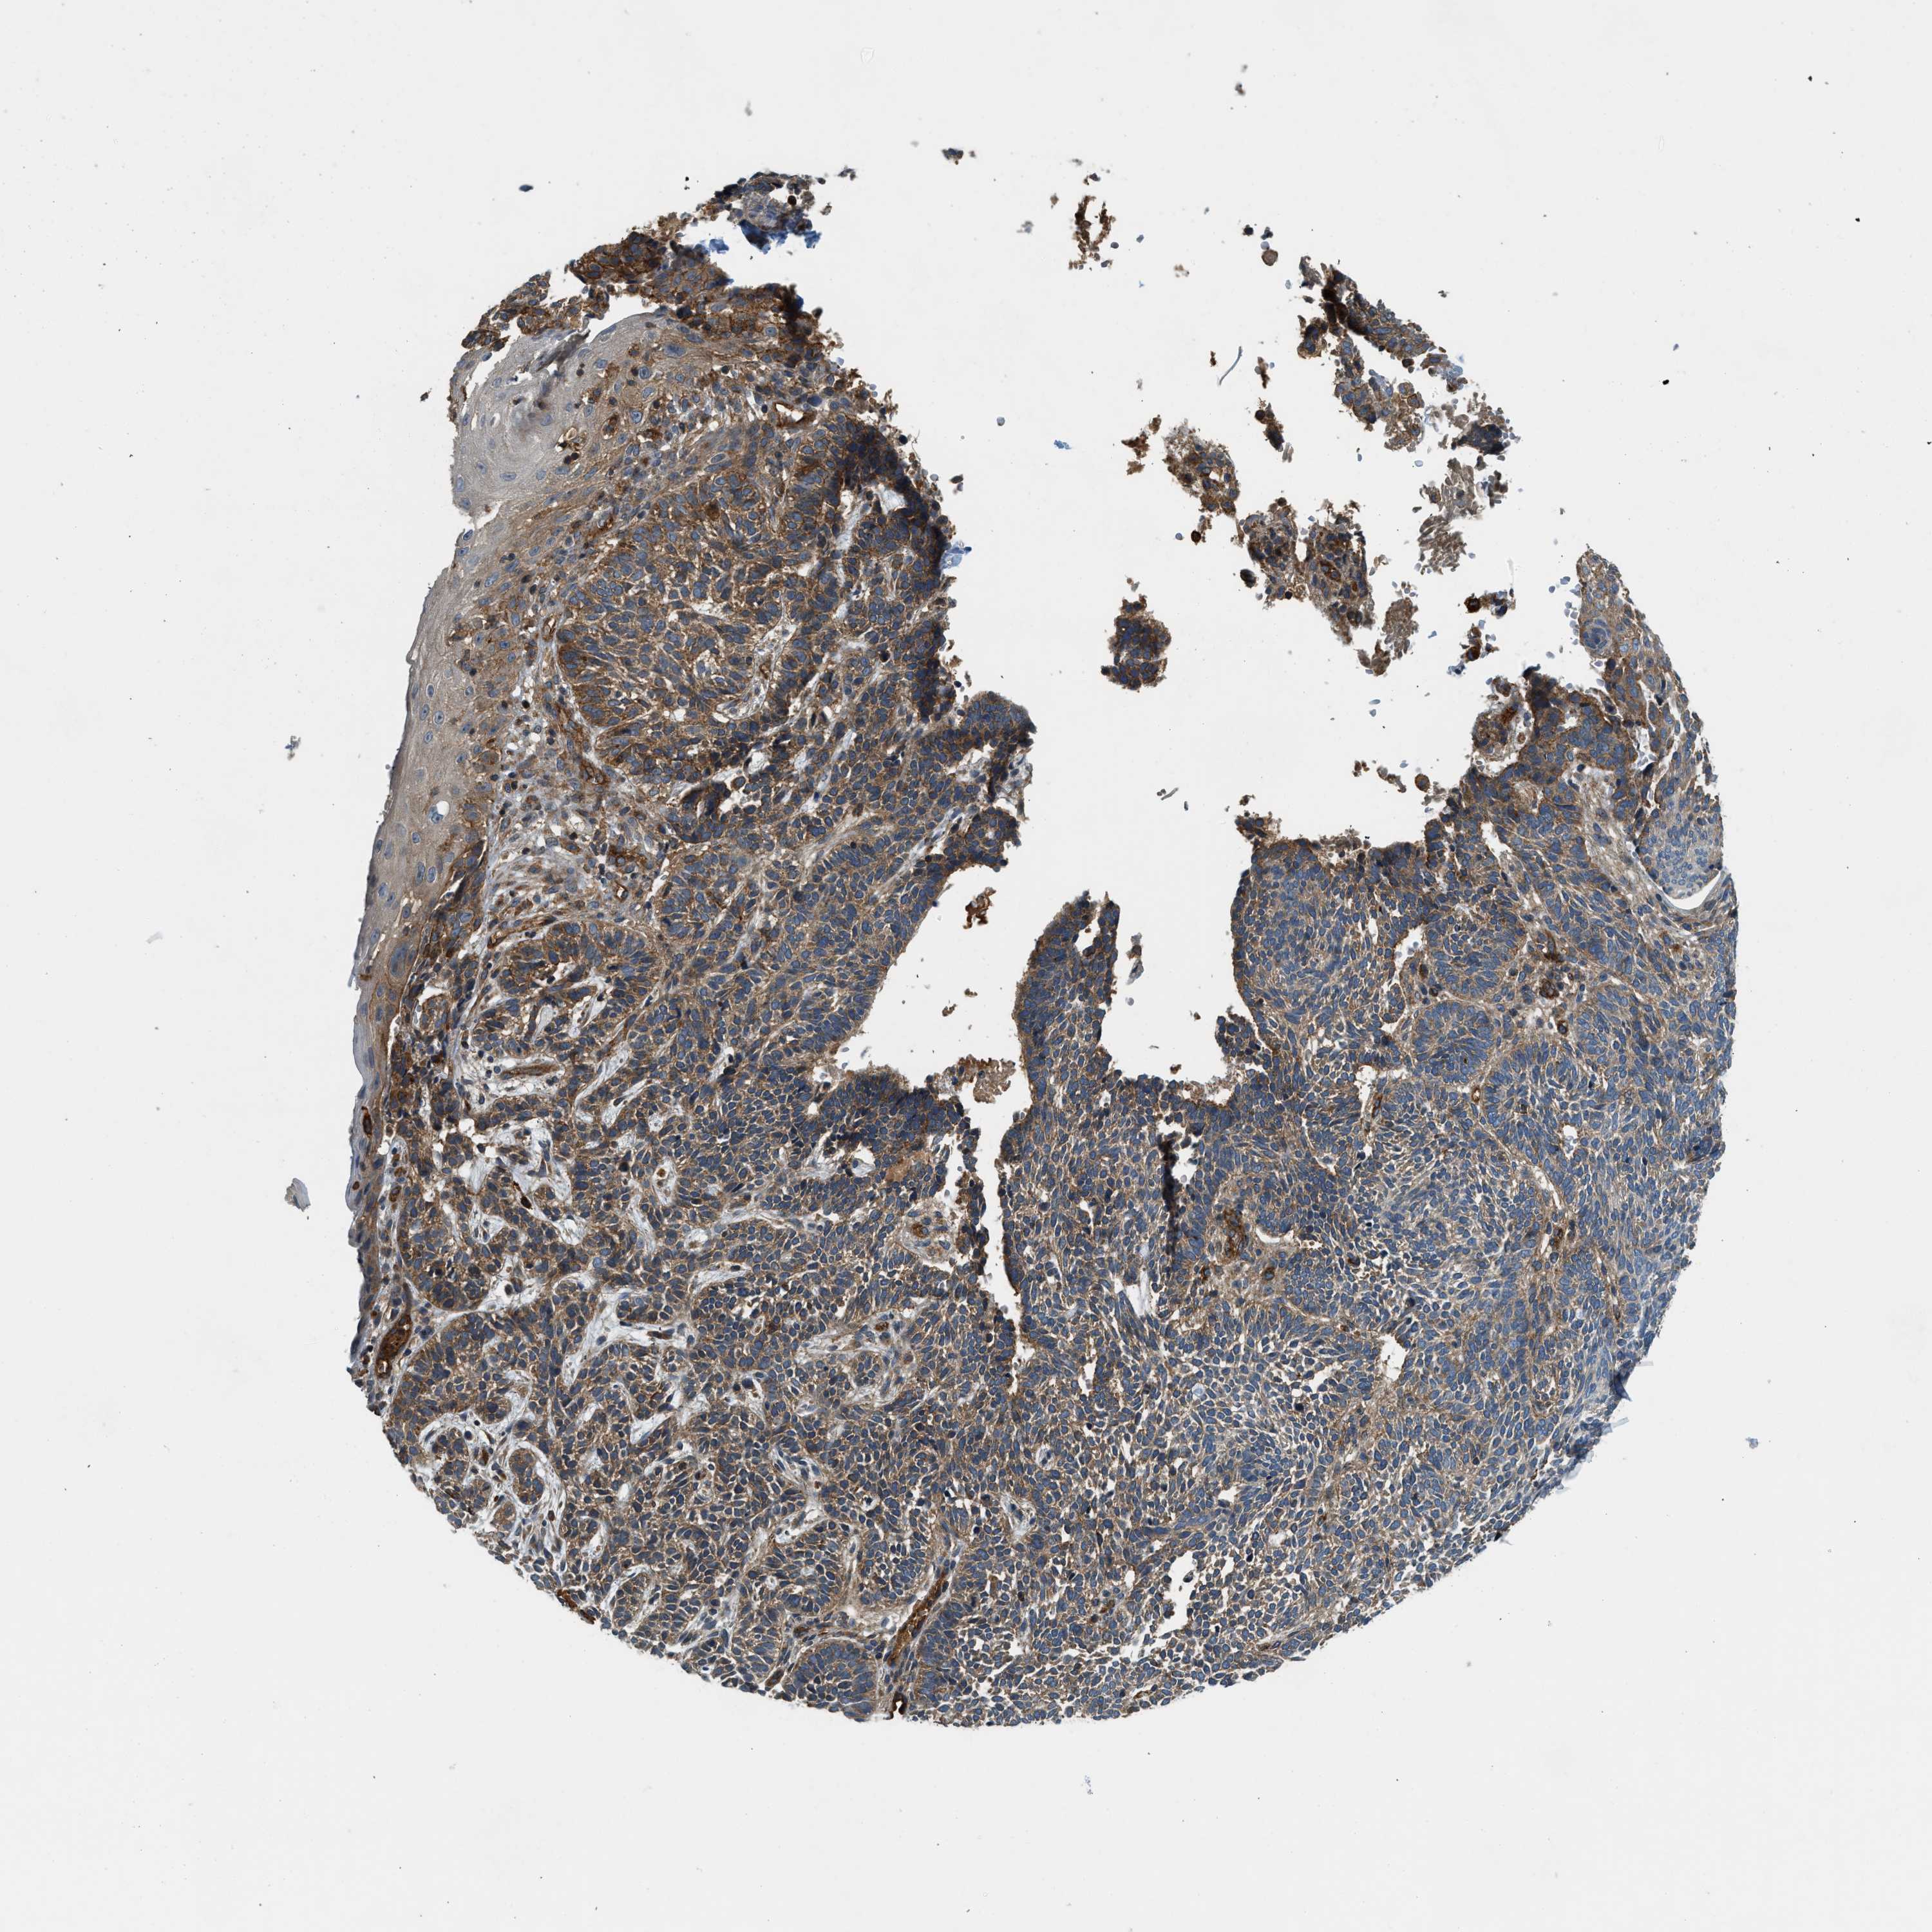

SKIN CANCER - Protein expressioni

A mouse-over function shows sample information and annotation data. Click on an image to view it in a full screen mode. Samples can be filtered based on level of antibody staining by selecting one or several of the following categories: high, medium, low and not detected. The assay and annotation is described here.

Antibody stainingi

Antibody staining in the annotated cell types in the current human tissue is reported as not detected, low, medium, or high, based on conventional immunohistochemistry profiling in selected tissues. This score is based on the combination of the staining intensity and fraction of stained cells.

Each image is clickable and will lead to virtual microscopy that enables deeper exploration of all samples and also displays staining intensity scores, fraction scores and subcellular localization as well as patient and tissue information for each sample.

Antibody HPA013606

Antibody HPA017964

Antibody CAB015334

Antibody CAB016402

Staining

High

Medium

Low

Not detected

Intensity

Strong

Moderate

Weak

Negative

Quantity

>75%

75%-25%

<25%

None

Location

Nuclear

Cytoplasmic/membranous

Cytoplasmic/membranous,nuclear

Squamous cell carcinoma in situ, NOS

Squamous cell carcinoma, NOS

Squamous cell carcinoma, metastatic, NOS

Basal cell carcinoma

Adnexal tumor, benign